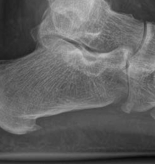

Contraindications to Immediate Plate Fixation

Immediate internal fixation is strictly contraindicated in the presence of compromised soft tissues. The "wrinkle sign" must be present before definitive surgical incisions are made. Operating through fracture blisters, severe ecchymosis, or massive edema exponentially increases the risk of deep infection and wound dehiscence. In such scenarios, damage control orthopedics utilizing joint-spanning external fixation is mandated until the soft tissue envelope recovers.